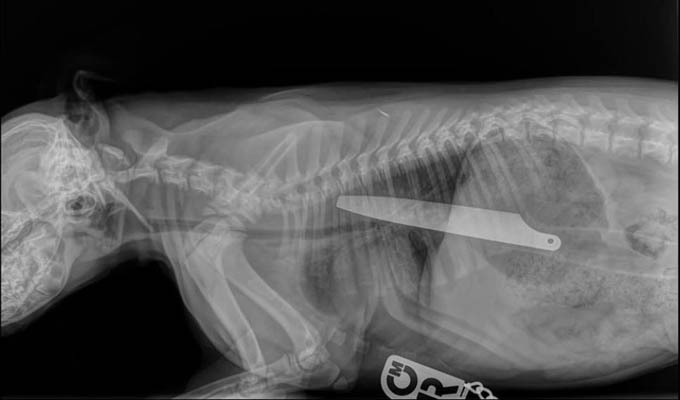

Un can logró sobrevivir después de comerse un cuchillo de cocina de 20 centímetros y ser operado de emergencia. La navaja se puede apreciar en una radiografía que le hicieron “Macie”, minutos antes de la intervención.

El cuchillo pasó por el estómago del perro, un Staffordshire Bull Terrier, y llegó hasta los intestinos, mientras que la punta de la navaja permanecía en su garganta, informa The Telegraph.